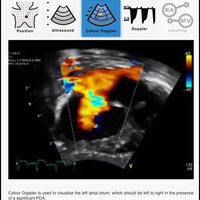

The purpose of this application is to support neonatologists who are actively involved in a recognized TnECHO training program. This application includes videos of probe position, 2D echo loops, color Doppler loops, and labelling of the various structures. This application is aimed at familiarizing neonatologists with basic echocardiography views and aiding self directed learning, but does not represent complete training. This application has not been designed to teach how to screen, diagnose or evaluate congenital heart disease, although it is recognized that neonatologists must be familiar with normal anatomy and deviations from this. Although structural heart disease should always be considered when performing a TnECHO evaluation, if the former is clinically suspected a paediatric cardiologist should always be involved. Image optimization techniques are not discussed as it is usually machine specific.